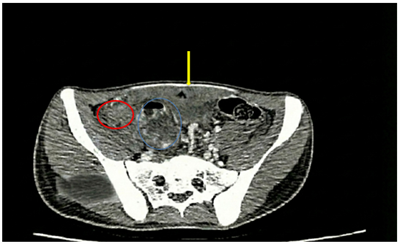

Chẩn đoán và điều trị bệnh nhân mắc đồng thời hai loại ung thư: Ung thư đại tràng và Ung thư dạ dày ở giai đoạn sớm tại Trung tâm Y học hạt nhân và Ung bướu - Bệnh viện Bạch Mai

Chẩn đoán và điều trị bệnh nhân mắc đồng thời hai loại ung thư: Ung thư đại tràng và Ung thư dạ dày ở giai đoạn sớm tại Trung tâm Y học hạt nhân và...

Ngày đăng: 09/09/2025

Ung thư đại – trực tràng và ung thư dạ dày là 2 trong 10 loại ung thư phổ biến nhất trên thế giới trong nhiều thập kỷ qua. Theo GLOBOCAN 2022, ở Việt Nam, ung thư đại trực tràng đứng thứ 4 về tỷ lệ...